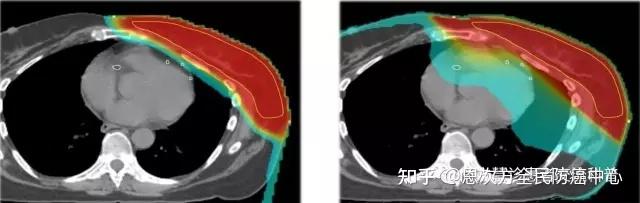

1、质子治疗乳腺癌:

可以看到,质子放疗时,放射剂量主要在乳腺靶区。而光子放疗时,放射剂量除了在乳腺靶区外,心脏和肺都受到了不必要的照射,产生长期的毒副作用。